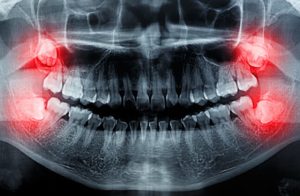

رادیوگرافی

رادیوگرافی دندانها میتواند به دندانپزشک کمک کند تا میزان تخریب استخوان و بافتهای حمایتی دندان را ارزیابی کند. این تصاویر همچنین میتوانند وجود تارتار و پاکتهای پریودنتال را نشان دهند.